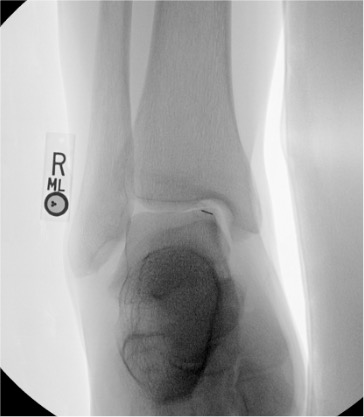

| Elbow | 3–5 mL | Fluoroscopy or ultrasound | Lateral (radiohumeral) approach | Triangle formed by lateral epicondyle, radial head, and capitellum; elbow flexed 90°; posterior fat pad elevation on lateral radiograph suggests intra-articular effusion and facilitates access |

Elbow

Needle placementPost-injection